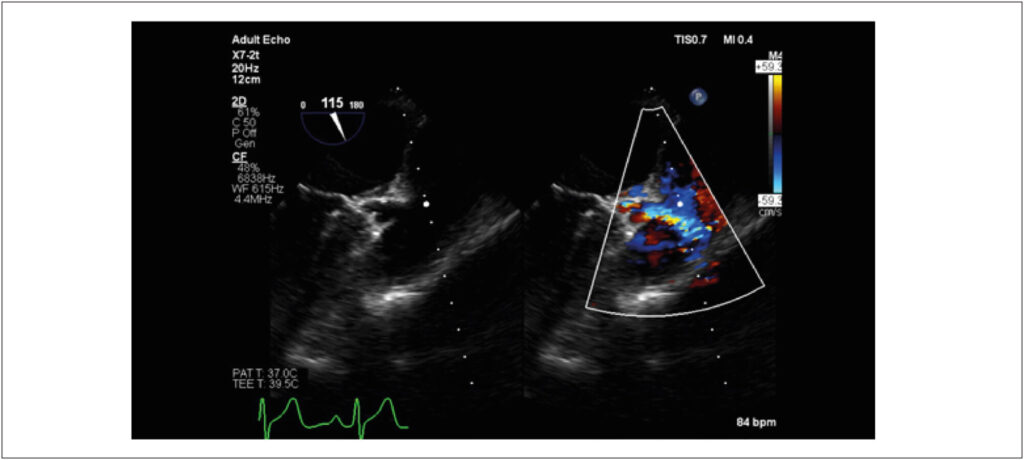

Paciente do sexo feminino, 33 anos, com queixas de palpitações, precordialgia e dispneia aos grandes esforços. Ecocardiograma evidenciou artéria coronária esquerda originando-se da artéria pulmonar com fluxo reverso e dilatação da artéria coronária direita (Figura 1 e Vídeo 1). Na sequência, foi realizada angiotomografia de coronárias, que corroborou diagnóstico de Origem Anômala da Artéria Coronária Esquerda a partir da Artéria Pulmonar (ALCAPA, do inglês Anomalous Left Coronary Artery from Pulmonar Artery), também conhecida como síndrome de Bland-White-Garland (Figura 2). Tal patologia representa uma alteração congênita rara e potencialmente fatal, com apresentação inicial infrequente em adultos.